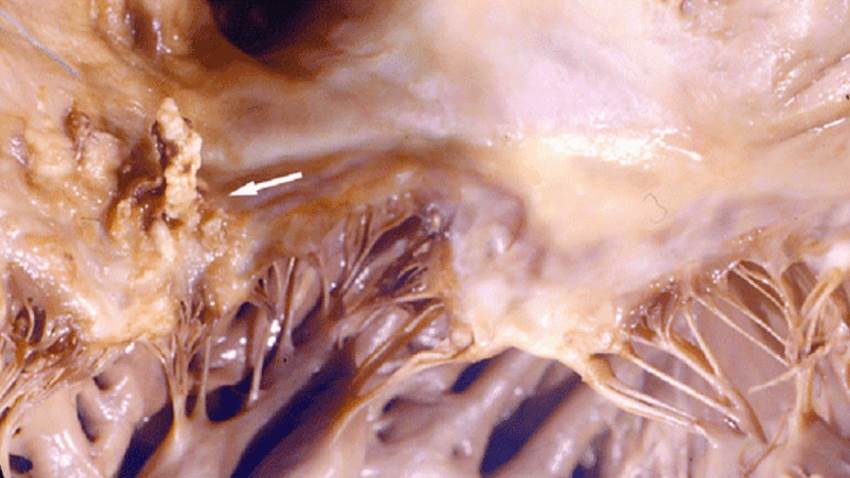

El tratamiento parental ambulatorio es seguro para la endocarditis infecciosa, según estudio

De acuerdo a la investigación, este tipo de tratamiento es una alternativa segura y eficaz con hospitalización para pacientes con endocarditis infecci...